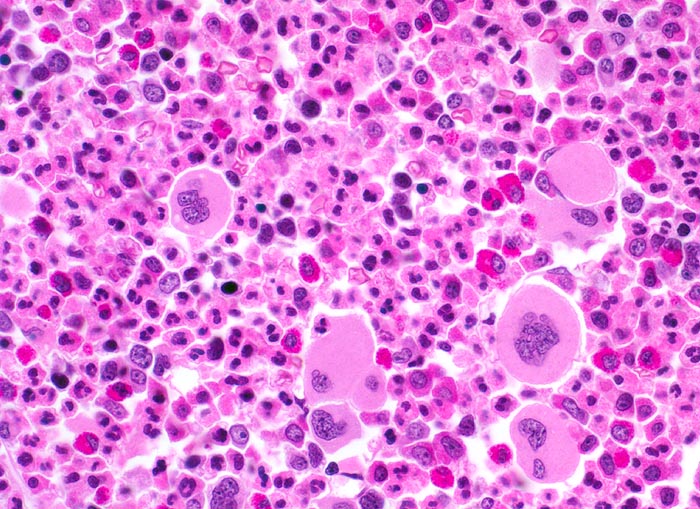

In der chronischen Phase zeigt das Knochenmark eine Hyperzellularität, welche auf eine Vermehrung der neutrophilen Granulozyten und deren Vorläufer zurückzuführen ist. Der paratrabekuläre Streifen unreifer Granulozyten kann verbreitert sein von normal 2-3 Zellschichten auf 5-10 Zellschichten. Blasten machen weniger als 5% der Knochenmarkzellen aus. Eine Blastenzahl von mehr als 10% deutet auf eine Transformation in ein akzeleriertes Stadium und von mehr als 20% entspricht einer Blastenkrise mit Transformation in eine akute Leukämie. Die Megakaryozyten sind typischerweise kleiner als normal, haben hypolobierte Kerne und sind bei 40-50% der Patienten vermehrt. Der Prozentanteil der erythroiden Vorstufen ist gewöhnlich vermindert (G:E Ratio >5:1. Die initiale Knochenmarkbiopsie zeigt bei 40% der Patienten eine Vermehrung von Reticulinfasern assoziiert mit einer erhöhten Anzahl Megakaryozyten. Das Ziel der histologischen Untersuchung des Knochenmarks besteht darin, den Anteil an Blasten im Knochenmark und damit das Stadium der Erkrankung festzulegen. Bis zu einem Blastengehalt von weniger als 10% der kernhaltigen Zellen spricht man von einer chronischen Phase, zwischen 10 und 20% von einer akzelerierten Phase und bei über 20% liegt eine akute Leukämie vor.

• Fast 100% Zellularität des blutbildenden Marks (praktisch keine Fettzellen, sogenanntes "packed marrow").

• Stark vermehrte, ausreifende Myelopoese.

• Der paratrabekuläre Saum unreifer myeloischer Zellen ist verdickt auf 5 bis 6 Zellen.

• Verdrängung der Erythropoese.

• In Gruppen liegende vermehrte nacktkernige (= kein Zytoplasma) verkleinerte Mikromegakaryozyten mit hypolobierten Kernen.